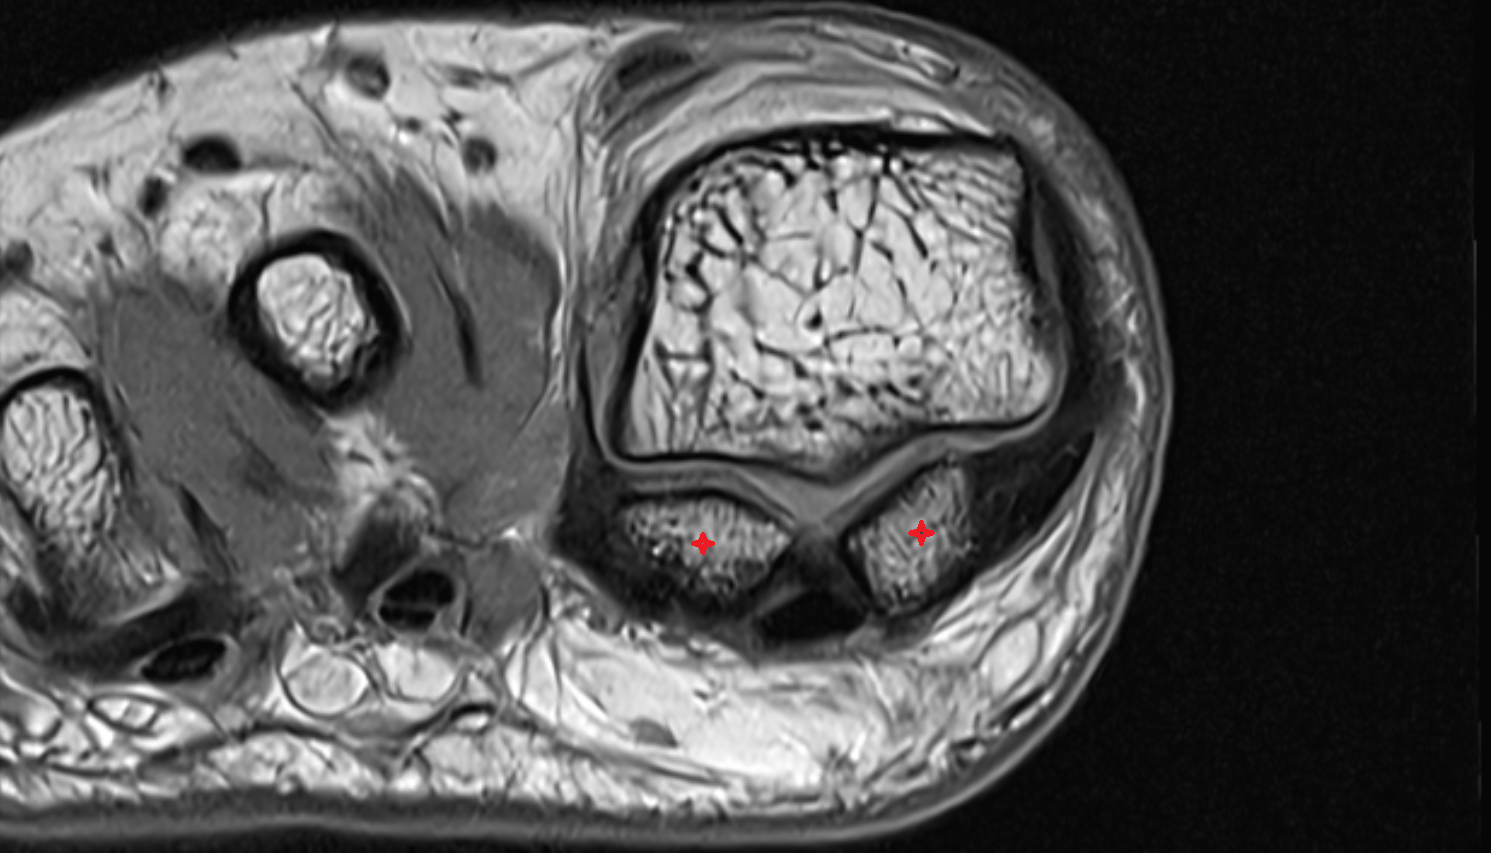

- Sesamoid bone of great toe

- Lateral sesamoid bone

- Medial sesamoid bone